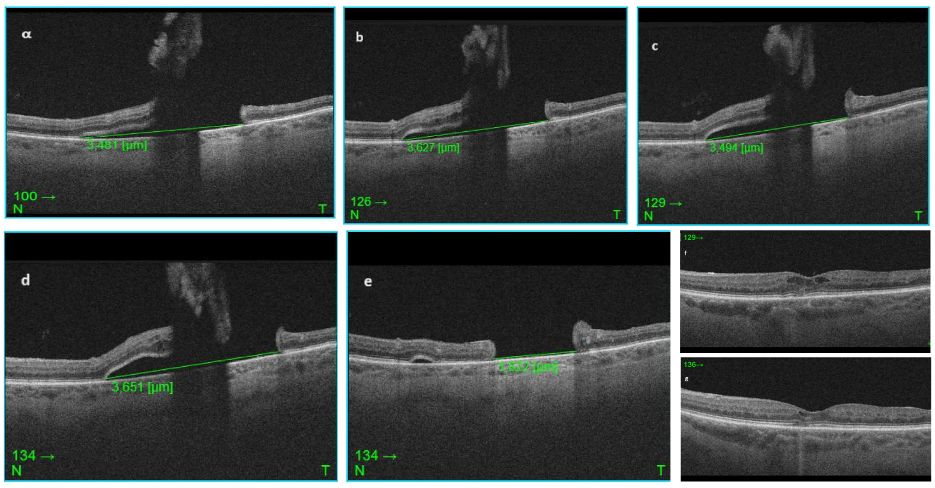

Figure 2: SD-OCT Images of the macular horseshoe tear through the same position demonstrating the change in the subretinal fluid at each follow up. The size of the fluid has been manually measured using the calipers of the Topcon software. a) shows the B-scan of the day of diagnosis with SRF size 3.481 µm, b) shows the scan at one week follow up, base of the tear measured 3.627 µm, c) at two weeks follow up, the SRF is reduced, base of the tear measured 3.494 µm but the retinal flap appears more raised and d) shows the one month follow up scan, where there is an increase in the amount of SRF size 3.651 µm and definite progression. e) post-surgical macular defect measuring 1.822 µm, flat, with no evidence of subretinal fluid or residual vitreous traction, f) and g) show pre- and post-surgical macular oedema.

At one week follow up, the patient’s vision was 6/12 (LogMAR 0.30) in the affected eye, the intraocular pressure 14 mmHg and her symptoms stable. No progression was evident on either fundoscopy or OCT imaging, where the base of the retinal tear measured 3.627 µm (Figure 2b [Fig. 2]).

At two weeks follow up, the left eye visual acuity was 6/15 (LogMAR 0.40) and the intraocular pressure 14 mmHg. No progression was recorded, and even a mild improvement in the SRF with the base of the tear measuring 3.494 µm was observed (Figure 2c [Fig. 2]).

One month after the original examination the patient noticed no change of the paracentral scotoma, her vision from the left eye was 6/12 (LogMAR 0.30), the intraocular pressure 12 mmHg, but it was noted that the subretinal fluid associated with the horseshoe macular tear had progressed (Figure 2d [Fig. 2]: base of the tear measured 3.651 µm).

The patient was monitored for 6 months following surgery, serial SD-OCT images demonstrated that the pathology was stable, with a retinal defect size of 1.822 µm (Figure 2e [Fig. 2]) and no evidence of new tears or breaks. Her final Snellen visual acuity 6 months after surgery was 6/6 (LogMAR 1) in the right eye (Nd: Yag laser was performed in this eye as well) and 6/15 (LogMAR 0.40) in the left, intraocular pressure 13 mmHg in the right and 14 mmHg in the left eye.